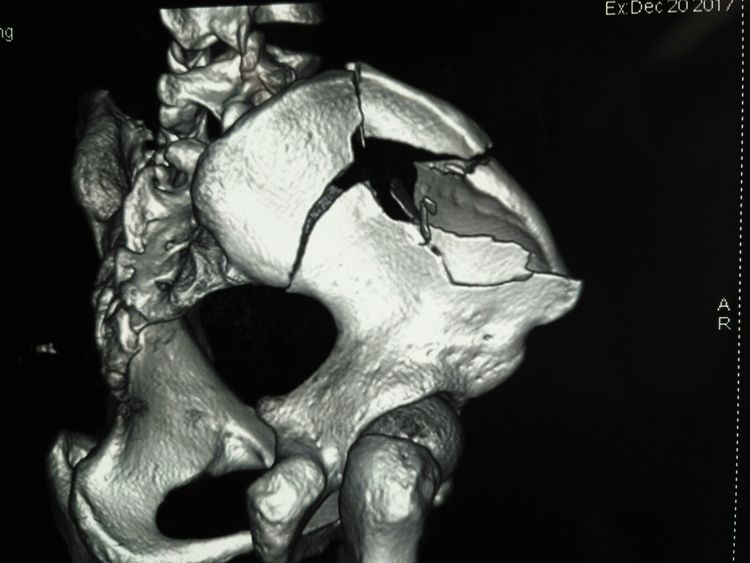

術(shù)前CT三維重建影像

術(shù)前CT三維重建